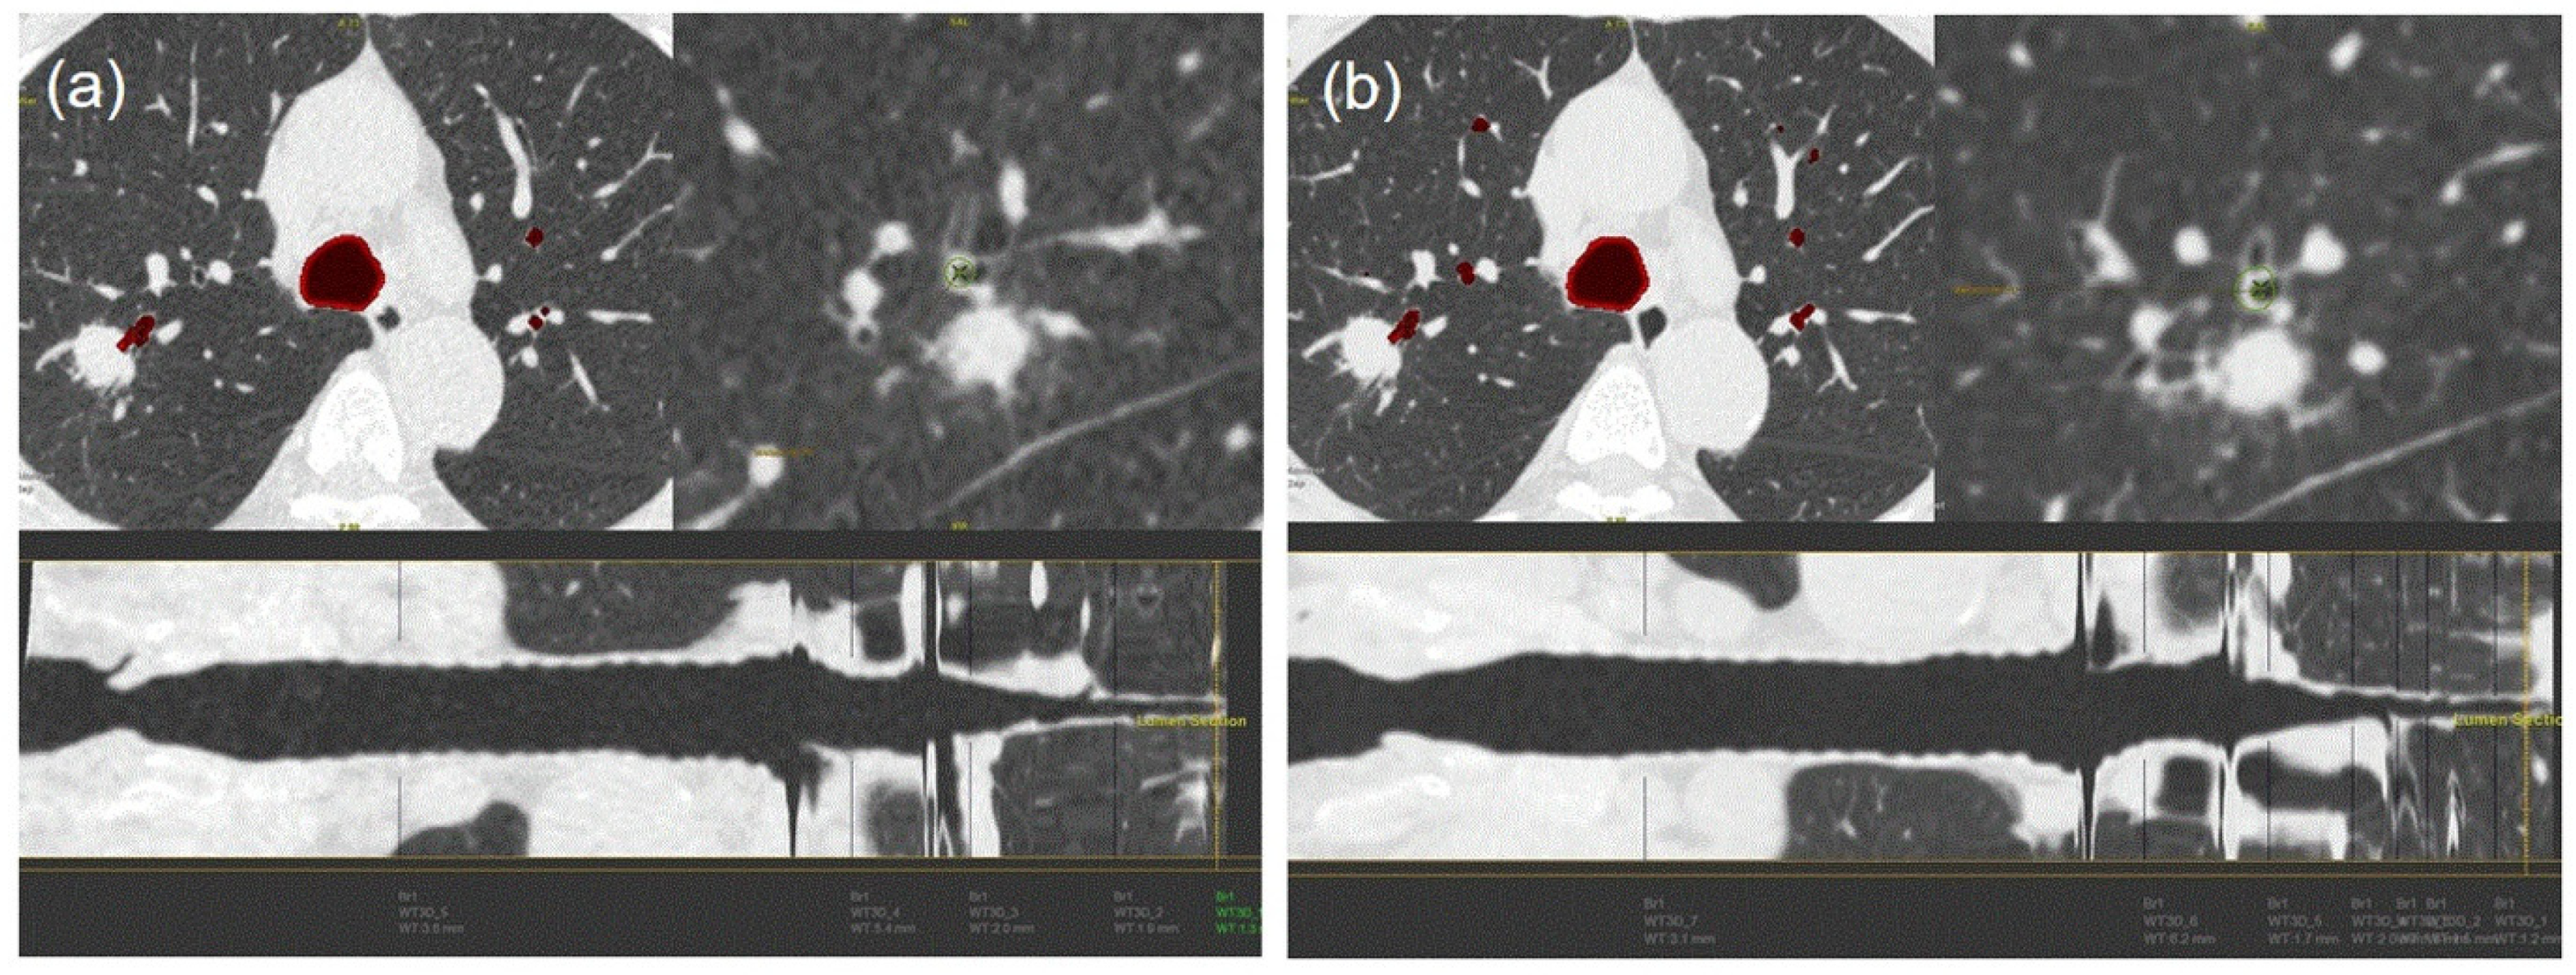

3.3. Bronchus Sign